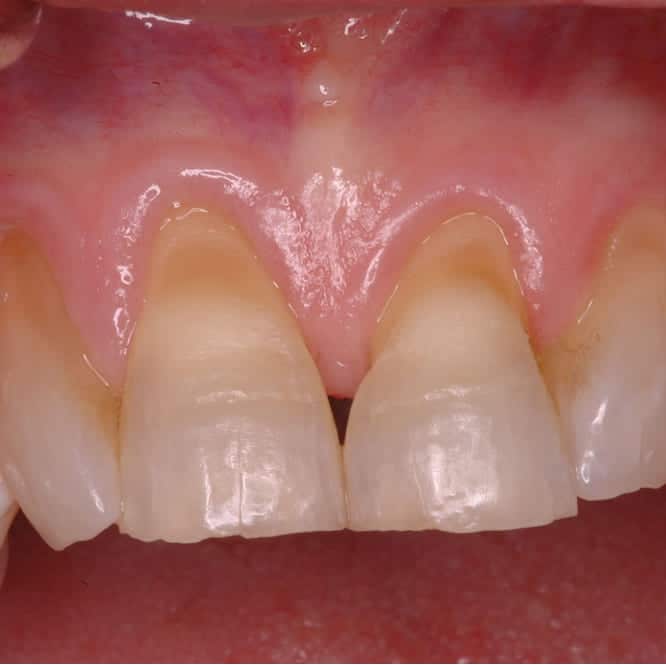

Before treatment showing worn, damaged teeth with irregular gum contours and compromised periodontal health Before

RW was 52 when he established care with a new general dentist following a move to San Diego. Years of bruxism, aggressive brushing, and inconsistent dental attention had taken a quiet but cumulative toll — teeth were worn down, gum tissue was receded in some areas and irregularly overgrown in others, and the overall periodontal foundation was compromised.

RW presented with generalized moderate periodontal disease, localized areas of significant gum recession, uneven gingival margins, and clear evidence of long-term nighttime bruxism from the wear patterns on his biting surfaces. Cervical abrasion from years of hard-bristled brushing had carved notches at the gumline on multiple teeth.

The tissue was a study in contrasts — inflamed and thin in receded areas, fibrotic and thickened in zones that had been chronically irritated. Neither presentation was healthy, and the asymmetry between them had created an aged, uneven appearance across the smile.